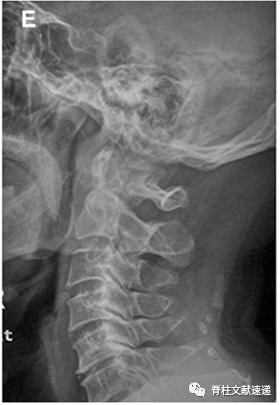

文献三

该文献进一步指出了项韧带骨化和OPLL的相关性,并举出3个病例,如下图。

总之,项韧带骨化是容易被忽视的X线征象,对诊断颈椎病或颈椎OPLL具有很大帮助。